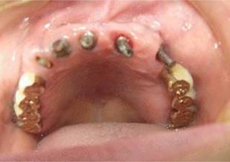

2008年度Ope前の写真です。10年近くなんとかしのいだという状態です。

| 10年前に彼女は仕事を持っていたため全顎の治療ではなく局所的な治療で終わっていました。審美的にも多くの問題があります。 |

残念ながらきれいな口腔内の状況とは程遠い状態です。